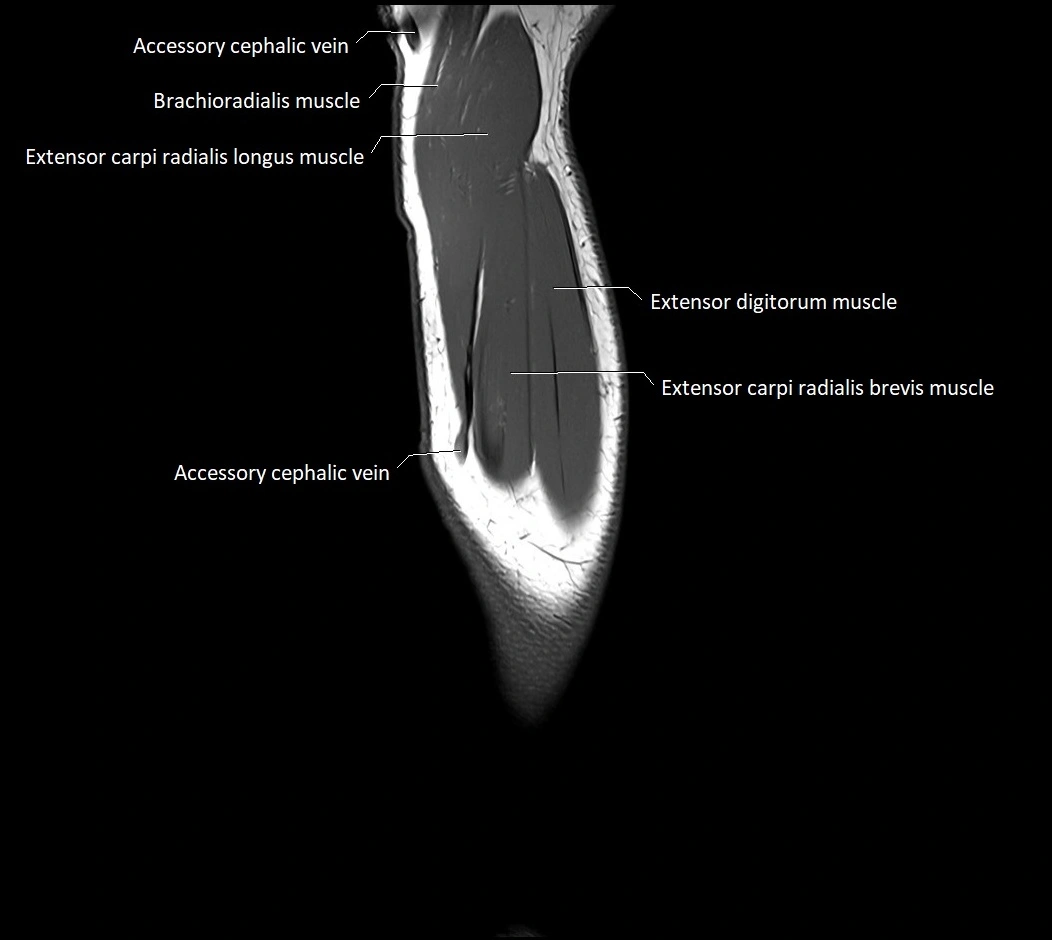

MRI images

image